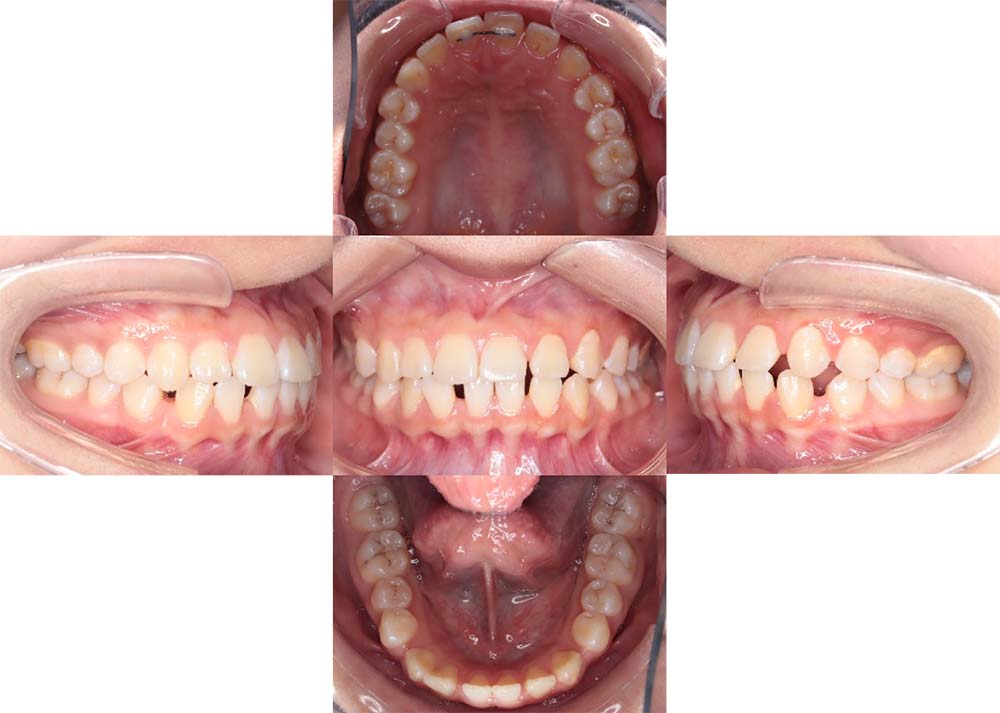

症例01

| 主訴 | 歯並びがガタガタしている。 |

| 診断名あるいは主な症状 | 叢生 |

| 年齢/性別 | 22歳・男性 |

| 矯正ステージ | 大人の矯正治療 |

| 治療方法 | ワイヤー矯正 |

| 抜歯部位/抜歯有無 | 非抜歯 |

| 治療内容 | 上顎大臼歯の遠心移動により前歯のガタガタを排列スペースを獲得し全顎的な排列を行った。 |

| 費用 | 85万円程度(2025.10時点の料金となります。) ※矯正基本料金、審美ブラケットを含む |

| 治療期間 | 2年4ヶ月 |

| 主なリスク・副作用 | 痛み、歯根吸収、歯肉退縮、虫歯、後戻り |